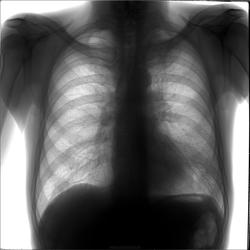

Этот случай с установленным диагнозом. Написала я его неправильно, хотя первая мысль была правильная, и на флэшку скинула его под правильным диагнозом, но тогда случай не стала выставлять как слишком понятный.. Мужчина 1955 гр пришел к нам в феврале с жалобами на кашель и слабость после выписки из больницы, где лежал с сотрясением мозга. В больнице обнаружили изменения и отправили на дообследование по месту жительства. Объективно мужчина бледный, худой. Какие будут мнения?

Вроде как инфильтрат в левой верхушке.С дорожкой к корню.Внизу слева вероятны отсевы.

Правильно-неправильно, расценил бы как туберкулез.

Аналогично. ТВС вне конкуренции.

Туберкульоз инфильтративный с дессименацией. Если б не отсевы внизу можно было бы подумать еще про периферический рак. Пенкоста, например.

С задним отрезком 7 ребра слева все нормально?

Пациент нами был отправлен в тубдиспансер.. Оттуда после долгого обследования пришел ответ - Neo, метастазы. Туберкулез исключен. Насчет локализации опухоли не сказали..

Так что это односторонний карциноматоз

это центральный рак слева? Объём легочного поля слева уменьшен, корень расширн, гиповентиляция...

Да, возможно опухоль по типу панкоста, как кто-то написал, а внизу уже метастазирование

проявляется метастазирование? Все легочное поле слева пониженной прозрачности, средостение смещено влево.

Здесь на сайте может быть не очень видно - там не просто понижение прозрачности, а усиление легочного рисунка и мельчайшие очаги